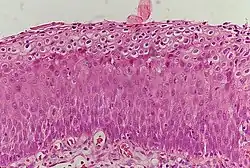

La NCI est classée en grades[14] :

| Grade histologique | Cytologie correspondante | Description | Image |

|---|---|---|---|

| 1 (catégorie I) | Lésion malpighienne intra-épithéliale de bas grade (LSIL) |

|

| 2/3 | Lésion malpighienne intra-épithéliale de haut grade (HSIL). |

| |

| 2 (grade II) |

| ![]() | |

| 3 (grade III) |

| ![]() |